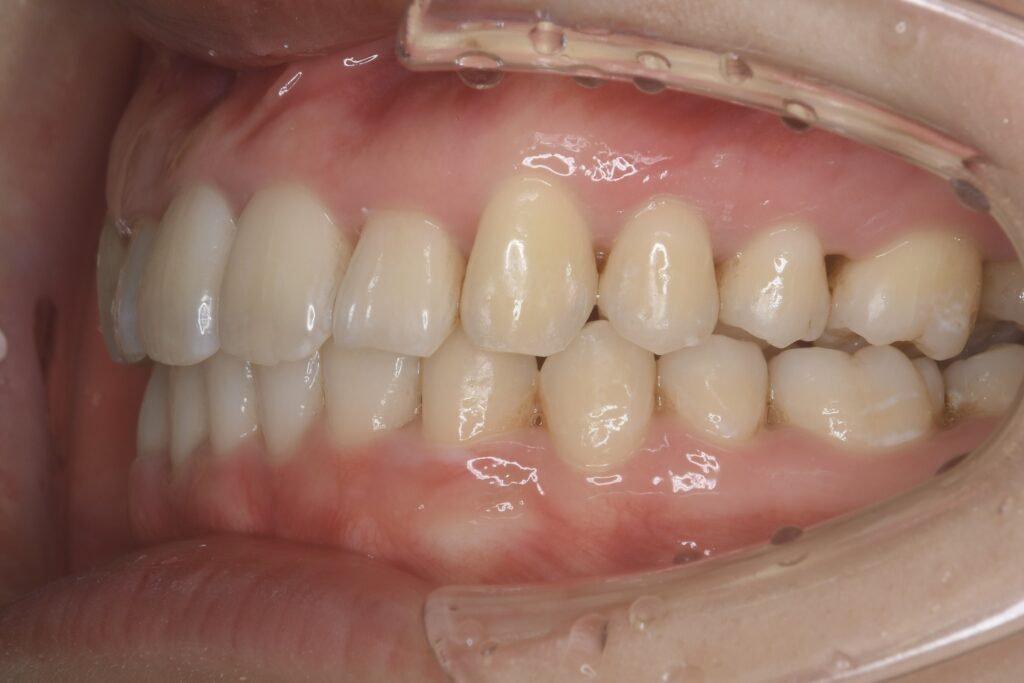

21歳 女性 治療期間:1年1ヶ月

叢生(ガタガタ)

マウスピース矯正装置(インビザライン)

非抜歯

BEFORE

AFTER

診断名・主な症状

叢生

治療内容

上下とも歯並びの横幅を広げながら、でこぼこを解消しました。

マウスピース矯正(インビザライン)

抜歯あり(智歯抜歯)

治療期間

1年1ヶ月

通院回数

10回

費用

85万円程度(税別)

リスク・副作用

痛み、歯肉退縮、歯根吸収、抜歯に伴う出血や腫れが生じることがあります。